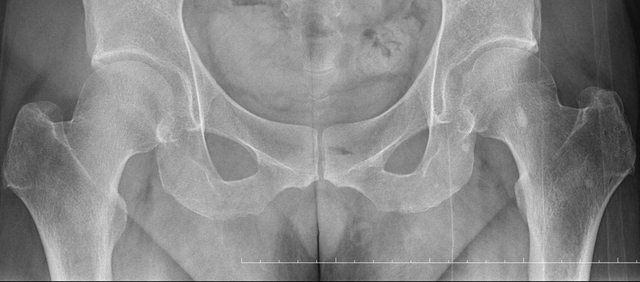

骨盆 https://i.imgur.com/h7KknkX.png

股骨頭放大特寫...左邊是右股骨 你覺得哪邊比較正常? https://i.imgur.com/16erxqZ.png

醫生似乎很急 就問了二個問題就叫我去照X光 可能就一分鐘吧 回來看了下X光就說可能有神經壓迫 又是14天的消炎止痛藥 說還會痛再來回診或去看脊柱專科或復健科 感覺就是浪費了一天的時間排隊再排隊 沒得到答案 也沒有得到解決... 然後拿了吃越多可能洗腎越快的止痛藥 會不會下次脊柱專科也開14天消炎止痛說如果還有問題叫你去掛神經科? 為何不給我照MRI呢?我第一次去看問了MRI就還是只給我照X光 1.2期X光照了也不一定有異常,我實在不懂不用MRI的邏輯 體驗實在太差了,當然我也知道當有一百號排隊時問診就不可能細到哪怕只有15分 我想不等直接掛看看禮拜三神經科會怎解釋了 ※ 編輯: capybaradash (118.166.44.25 臺灣), 07/31/2023 14:29:17 ※ 編輯: capybaradash (118.166.44.25 臺灣), 07/31/2023 14:37:27

看了下治療方法,那有看等於沒看了 照MRI似乎也是白做,自費照根本浪費 其實X光以我外行人放大好幾倍看過去,左股骨跟大腿骨明顯狀態較差 不清楚醫生是不是有鷹眼,小小一張看過去就說沒什問題 我是不會去考慮手術的 小時候骨折都是看國術館 還減壓股頭打孔...開刀100%NO 治療方法 1.拐杖 2.藥物治療(1)非類固醇類消炎止痛藥(NSAID) (2)口服雙磷酸鹽類藥物 (3)血管擴張劑 (4)高壓氧 目前股骨頭缺血性壞死的治療,根據現有的證據,仍然以手術為主流。 於早期(第一、二期),尚未塌陷的股骨頭缺血性壞死,髖關節減壓手術值得一試, 至於第三、甚至第四期股骨頭缺血性壞死,人工髖關節置換術能夠有效的解除疼痛以及恢 復行走負重的功能。 ※ 編輯: capybaradash (118.166.44.25 臺灣), 07/31/2023 16:04:20

g17321732: 1.骨頭看起來沒大問題,x光不是放大找不一樣這麼簡單 07/31 18:18

g17321732: 3.MRI對你的幫助不大,X光已經足夠清楚,不用花冤枉錢 07/31 18:18

yasmine1030: 人體不是百分百對稱我實在看不出你X光兩邊股骨有何差 08/01 01:29